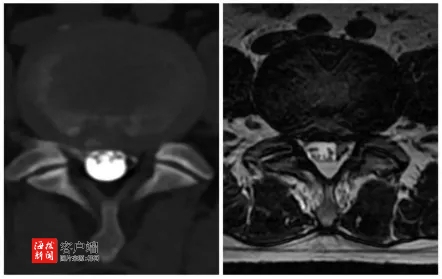

在仔细询问了李奶奶的病史后,孟教授又进行了一次全面而细致的体格检查,力求不错过任何可能导致疼痛的线索。经过深入的诊断,孟教授凭借他敏锐的医学洞察力,明确李奶奶患有腰椎椎管狭窄症,并用浅显易懂的语言,向李奶奶详细解释了她的病情,描述了腰椎椎管狭窄症的影响,以及它如何成为李奶奶长期疼痛的根源。

面对治疗方案的选择,孟教授提出了一项创新的微创手术——计算机导航下行斜外侧入路腰椎融合术。这种手术不仅能有效地缓解李奶奶的疼痛,还能恢复腰椎的稳定性。且手术创伤小,恢复期短。